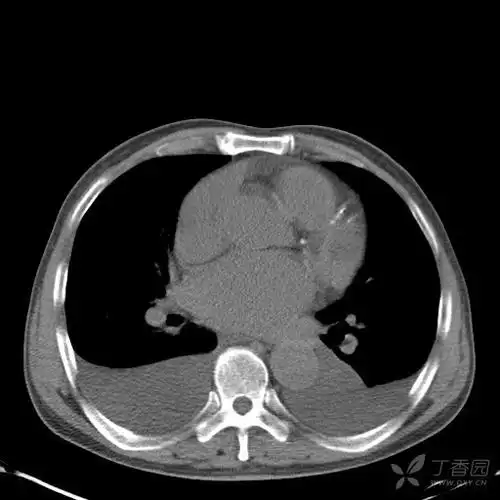

青年男性的胸腔积液